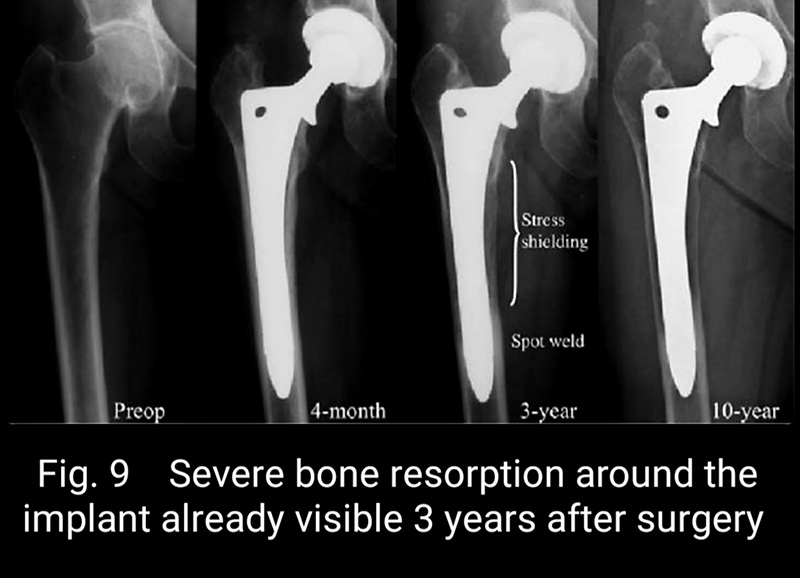

Short stems offer numerous advantages. First, with some short stem designs, a majority of the femoral neck is preserved. Surgically, this requires less surgical dissection and mitigates soft tissue and bone damage. Retaining the femoral neck has significant mechanical advantage in reducing both axial and torsional loads, as well as restoring the center of rotation of the femoral head in the sagittal plane (respect the anterior offset) improving hip balance (Fig. 6), and in the coronal plane (respect horizontal offset) improving abductor strength (Fig. 7 and Fig. 8). Ultimately, preservation of the femoral neck provides a more natural barrier to migration of particulate debris, is associated with less blood loss and less time and energy to rehabilitate the hip, reduces stress shielding of the proximal femur (i.e., load redistribution and subsequent loss of proximal femoral bone mass) (Fig. 9), and reduces end-of-stem thigh pain (spot weld Fig.9).